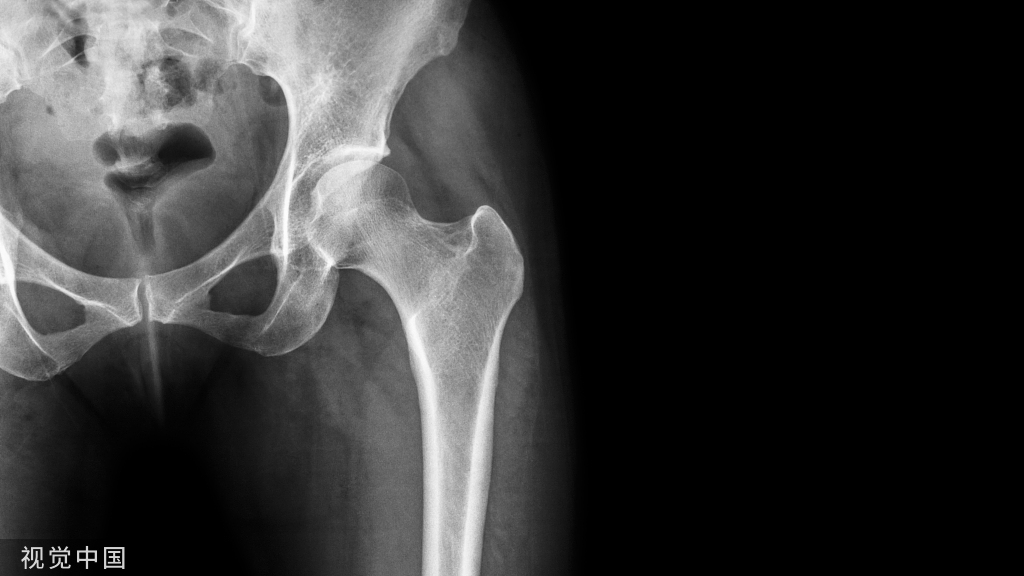

3岁因股骨干骨折行弹性髓内钉治疗,15年一直未取,现局部钉尾处不适要求取出。推测股骨长长的潜力是否近端优于远端。